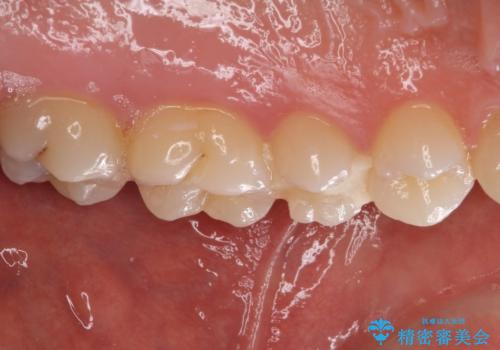

仮詰め材を外すと虫歯が残っていたので、全てを取り除いた後に、ゴールドインレーの型どりを行いました。

ゴールドインレーをご自身で選択いただいたものの、どういった仕上がりとなるか不安を感じていたようですが、実際に装着された口腔内をご覧になり、思ったほど金属色が気にならないとのことでした。

咬んだ感触はご自分の歯のときと比べ全く遜色なく、患者様には大変満足していただきました。